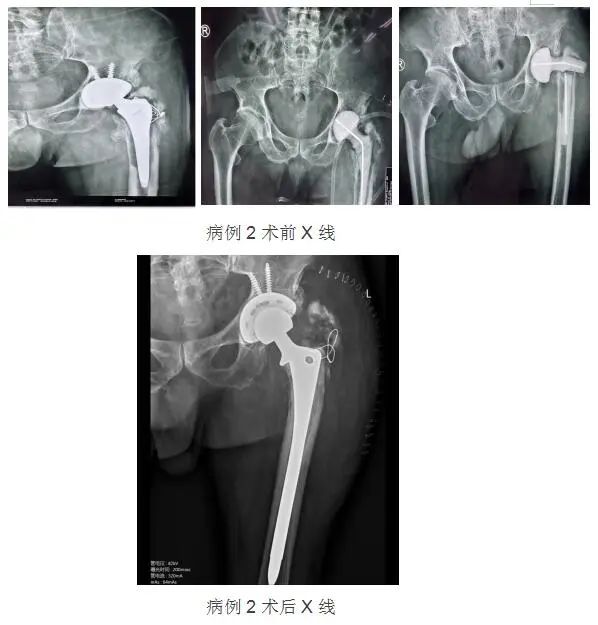

病例2:

男性,68岁,因“左髋疼痛,活动受限10余天”来诊。6年前因“股骨头坏死”行全髋关节置换术,2月前行左全髋置换术后假体松动取出+左髋病灶清除术+骨水泥占位器植入+髋关节旷置术,不久前又出现骨水泥占位器断裂。